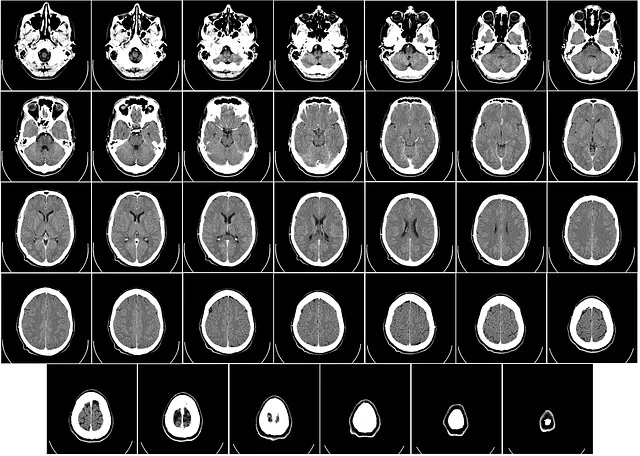

의료진은 영상 촬영 후 즉시 컴퓨터단층촬영(CT)으로 과도의 위치와 깊이를 정밀 분석했다. 이후 곧바로 응급 수술을 실시했고, 성공적으로 과도를 제거할 수 있었다. 현재 아이의 상태는 비교적 안정적인 회복 단계에 있는 것으로 알려졌다.